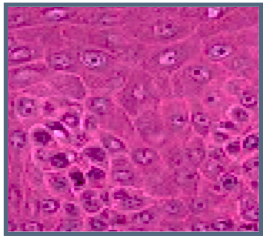

Give the name of this layer (be specific):

b. Stratum spinosum (polygonal cells, spines between adjacent cells)